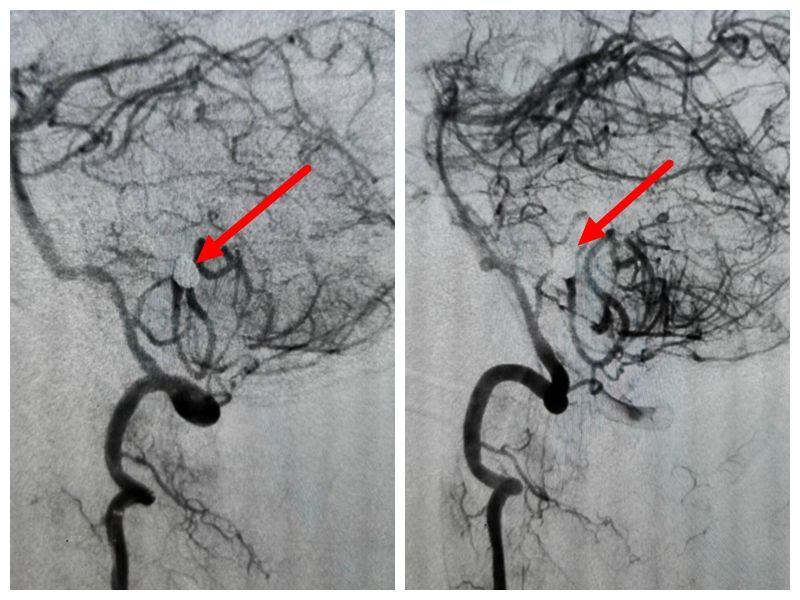

在没有头部外伤史的情况下,自发性蛛网膜下腔出血中50-80%是颅内动脉瘤这个颅内“炸弹”破裂造成的。入院后王振华主治医师立即给病人做了脑DSA检查。

一颗“桃心炸弹”长在了患者左侧小脑后下动脉延髓背侧段。虽然不大,但是已经破裂的动脉瘤随时面临着再次破裂出血的风险,而颅内动脉瘤再次出血的死亡率可达50%左右。

经介入血管内动脉瘤栓塞治疗,手术过程顺利,动脉瘤栓塞彻底,载瘤动脉术后血运通畅。